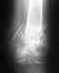

Снимок сделан 17.03 сразу после снятия гипса. Более свежих снимков у меня нет, но постараюсь сделать.

Если эти снимки свежие, то есть смысл переделать остеосинтез - убрать пластину по возможности малоинвазивно, и сделать внутрикостный блокированный остеосинтез. Который и следовало бы сделать изначально.

Насчет полной нагрузки - как-то по этим рентгенограммам это чересчур оптимистично.

Причём сказано это было абсолютно уверенно после первого же взгляда на снимки (правда, сначала было высказано несколько отборных крепких слов в адрес оперировавшего...). Может тут повлияло плохое качество репродукции и не всё видно на прикрепленном снимке?

Александр Николаевич, доброго времени суток!

Вот что в итоге получилось, снимки от 13 января 2010 года. В феврале убрали пластину, т.к. были боли в ноге в определенных ситуациях, например, при беге. Хотелось бы, если Вам не сложно, услышать оценку оставшейся деформации,насколько это критично в будущем (сейчас вроде всё ОК). Наверное, пора бы уже и позабыть, но всё ж терзают смутные сомнения, правильно я поступил, что не стал переделывать...Спасибо заранее.